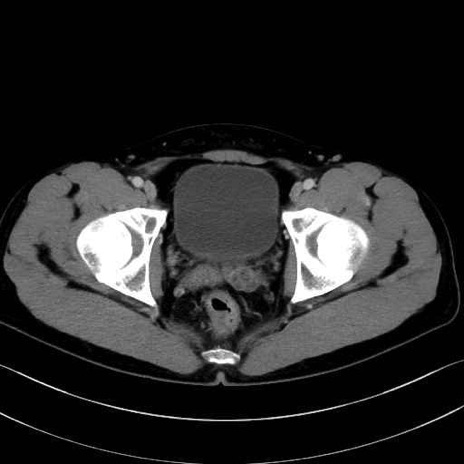

梨状筋(piriformis muscle) のCT画像の解剖

内閉鎖筋 (Obturator internus)